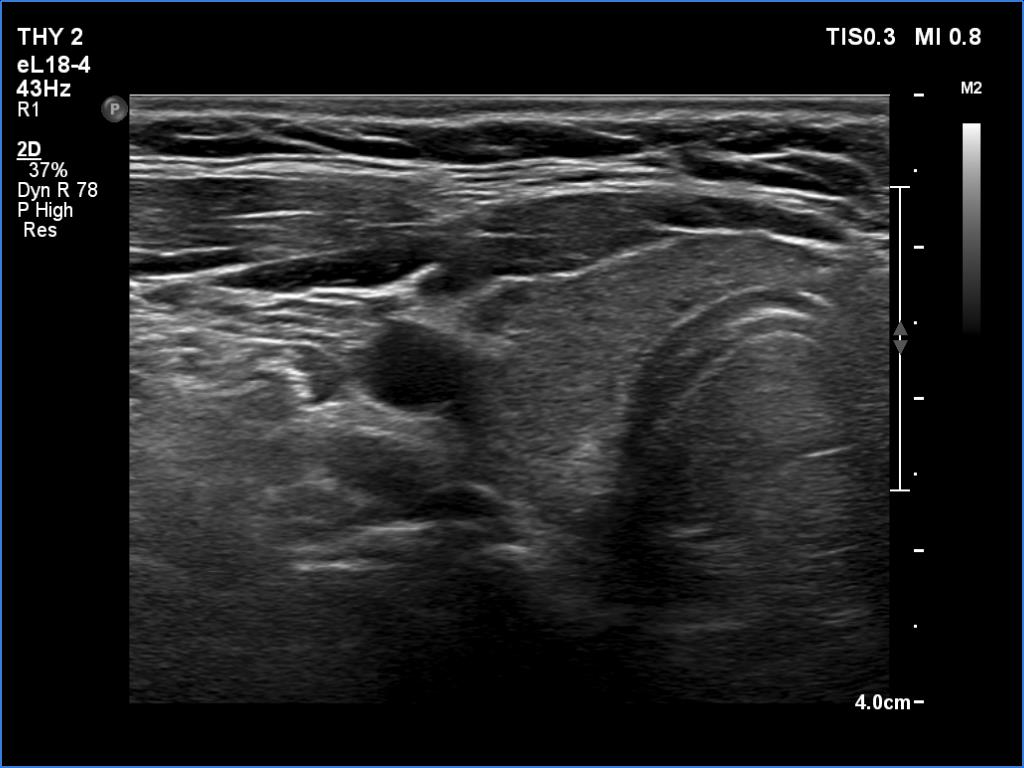

First examination (first and second rows of images):

Ultrasonography. The thyroid was echonormal or minimally hypoechoic and had several discrete, more hypoechoic areas. Two of them in the left lobe were remarkable because of irregular borders and nonparallel orientation.

Cytology was performed from the larger lesion in the left lobe and resulted in Hashimoto's thyroiditis.